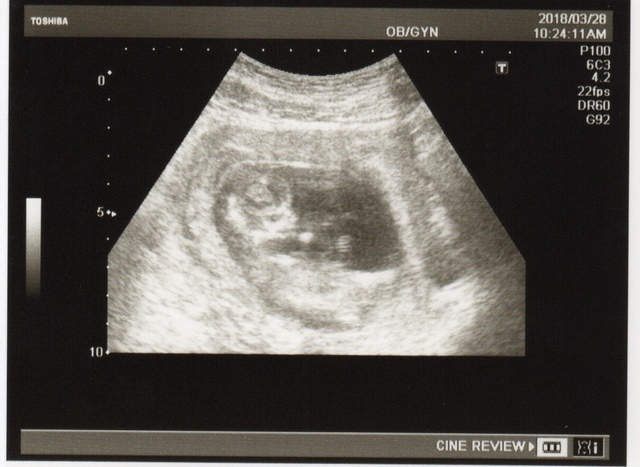

14週6日(14w6d・性別不明)|むむむーさん さん(36歳)

エコー写真撮影時のエピソード:

初めて正面からのお顔を見せてくれました(^O^)/ 残念ながら体は胎盤に隠れて見えず…

小さい手でお顔をこすってるような仕草を見せたりとかわいくてとーさんもニコニコ(^ω^) 早く性別が分かりたいなぁ!